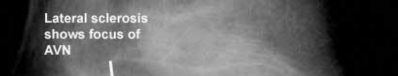

A 46-year-old competitive cyclist falls while racing and suffers an isolated fracture as seen in Figure A. He is positioned on a fracture table and a closed reduction maneuver is attempted, unsuccessfully.

When standard closed reduction maneuvers using a traction table are unsuccessful, displaced femoral neck fracture in young adults (10 degrees varus/valgus or anteversion/retroversion) or has

significant displacement (5 mm or more in ANY view) is unacceptable, and an open reduction should be performed. Of course, this can be very difficult to assess in the operating room, where uncalibrated fluoroscopy with difficult to obtain tangential imaging is heavily relied upon to make this assessment.

Accordingly, when the quality of closed reduction is questionable, the best treatment plan is to obtain a better reduction with direct visualization of the femoral neck prior to fixation.

A systematic review of the literature by Pauyo, et al. cites numerous studies showing a higher incidence of osteonecrosis of the femoral head in patients with displaced femoral neck fractures treated with unsatisfactory reductions. Furthermore, performing multiple closed reduction attempts is also associated with a higher risk of osteonecrosis.

Upadhyay et al. performed a randomized controlled trial of 102 patients with femoral neck fractures treated with closed or open reductions, which were randomized. The groups had similar rates of nonunions and osteonecrosis of the femoral head; however, subanalysis revealed a "poor" reduction was the highest predictor of poor outcome, whether the reduction was attempted open or closed. Interestingly, the quality of reduction was more important than the implant used or the timing of surgery (including surgeries performed > 48h after injury).

Figure A shows a pre-operative AP x-ray of the patient's high-energy femoral neck fracture. Illustrations A and B are intraoperative fluoroscopic and postoperative CT scans of this same patient, highlighting that fluoroscopy may "hide" the degree of residual displacement.